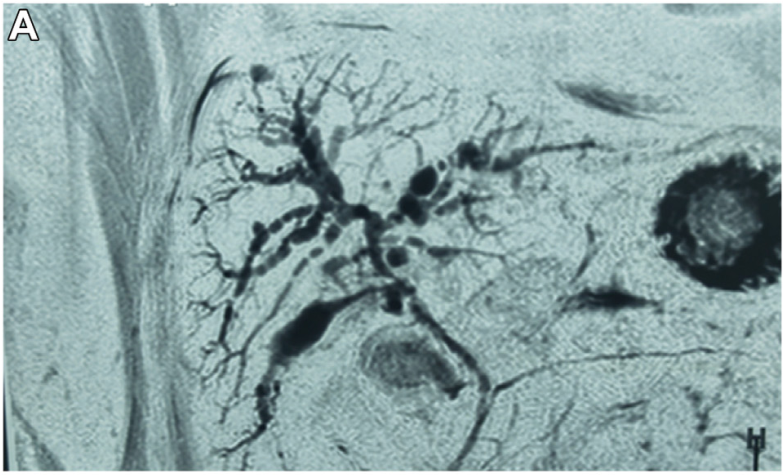

汤善宏教授:平原进入高原致血栓形成相关布-加综合征及门脉血栓复杂门脉高压病例分享

病史摘要:30岁男性,因“上腹不适6月,腹胀20天”入院。6月前无诱因出现上腹部不适、进食后腹胀,外院胃镜示反流性食管炎,肝功异常,对症治疗缓解。20天前出现全腹胀、黄疸、食欲降低、双下肢水肿。既往青霉素过敏,有吸烟、饮酒史,曾长期在高原工作。 诊疗过程:入院查体生命体征平稳,全身皮肤巩膜黄染,腹部膨隆,移动性浊音阳性。辅助检查提示布加综合征、肝硬化等。诊断为慢加急性